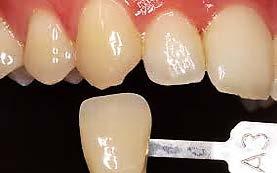

Estudio comparativo de la precisión entre 2 distintas técnicas

Las restauraciones indirectas son el día a día de la odontología, por lo tanto es de suma importancia conocer los diferentes sistemas para tomar impresiones dentales, ya sea convencionales o modelos digitales. Objetivo: comparar la precisión de la toma de impresión convencional con polivinil siloxano (Elite P&P) vs. el uso de una técnica de escanéo digital. Metodología: estudio transversal, comparativo, observacional e in vitro. En un tipodonto Nissin se realizó una serie de señalizaciones las cuales se fijan con cianocrilato para posteriormente tomar una impresión convencional, se fijan los vástagos con patern resin en la impresión y se vacía con yeso tipo IV de Zhermack, después se realizó un escaneo digital al tipodonto para así comparar

las distancias entre los diversos puntos marcados, esto con un vernier eléctrico. Resultados: se obtuvieron resultados ligeramente significativos entre las 2 distintas formas de obtener un modelo de trabajo. Conclusión: Según los hallazgos encontrados en este estudio, se determinaron las siguientes conclusiones: es de suma importancia utilizar los materiales como lo marca el fabricante. Los resultados obtenidos requieren estudios más precisos, pero pudimos determinar que los tiempos de trabajo son menores con la técnica digital, y por ende requiere menor ajuste.